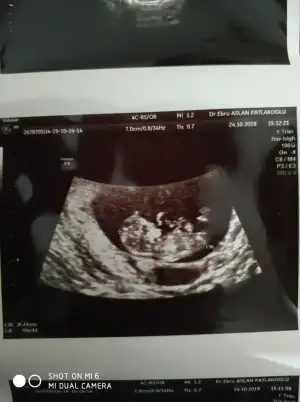

Buda 17 haftalik yeni hala ogrenmedin mi dersen ogrenemedimNet olmamakla birlikte kız sanki başka usg varmı 11 yada 12 hafta

12 haftalık başka yok maalesef haftaya gidecek testin sonucunu almayaKaç haftalık usg sanki erkek gibi başka usg varsa 11 yada 12 hafta tahmin ederiz

KızIkili taramada buda